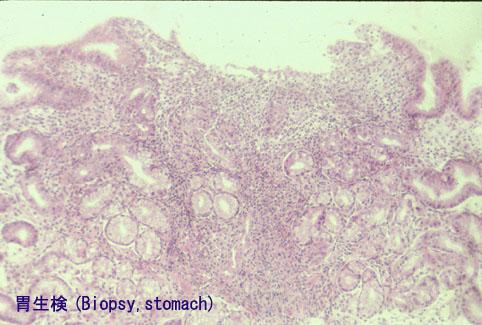

미소한 위병변을 동반한 소장과 대장 크론병의 절제례

염증성 및 궤양성질환/크론병

위(부위)/전정

마이크로